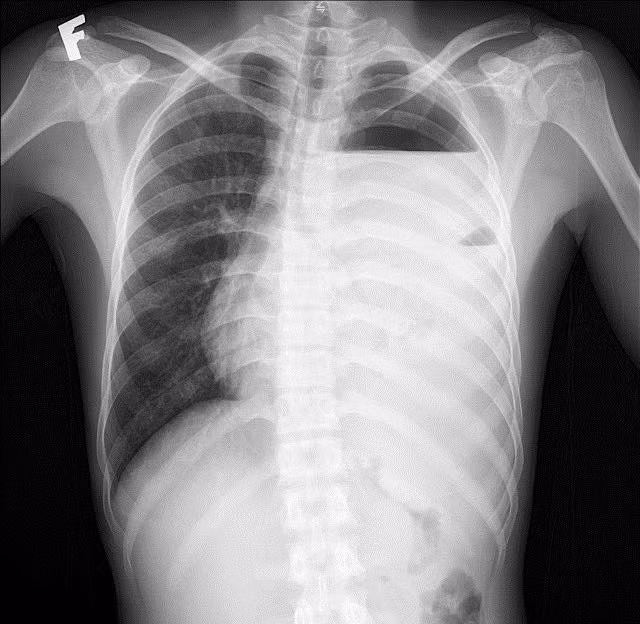

Hình ảnh phổi tổn thương trên phim chụp - Ảnh BVCC

Kết quả xét nghiệm máu cho thấy tình trạng nhiễm trùng nặng với chỉ số bạch cầu (WBC) lên tới 64.8 G/L, chỉ số CRP cao 263.6 mg/dL. Với hệ thống chẩn đoán hình ảnh hiện đại, các bác sĩ ghi nhận: Đông đặc nhu mô thùy dưới phổi trái, tràn dịch màng phổi trái lượng nhiều, tràn khí màng phổi trái, phổi trái bị xẹp thụ động, đẩy lệch trung thất sang phải.

Các bác sĩ khoa Ngoại Tổng hợp đã nhanh chóng đưa ra chẩn đoán: "Viêm phổi màng phổi trái biến chứng tràn mủ màng phổi" và chỉ định can thiệp ngoại khoa cấp cứu.